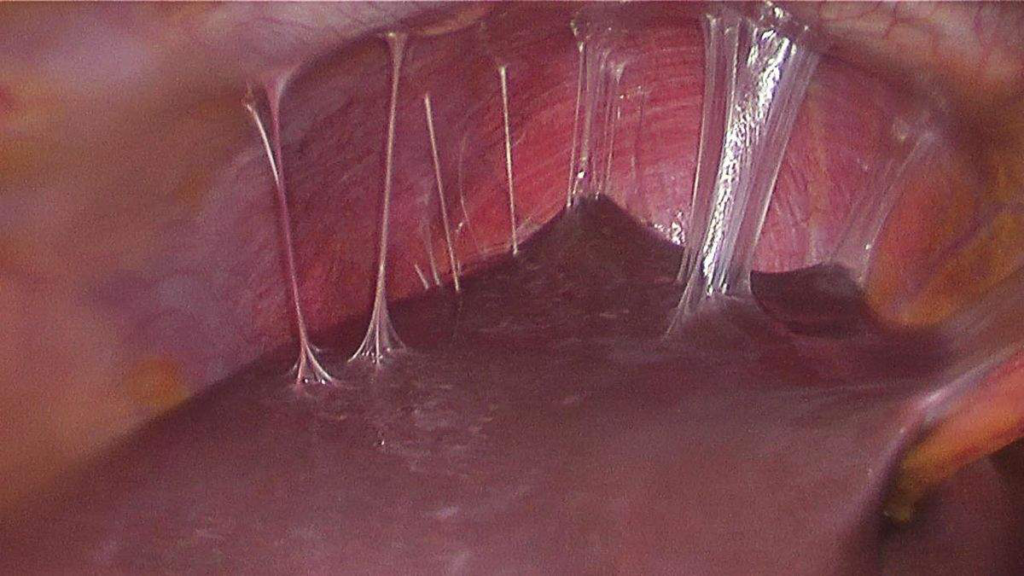

- Surgical drainage with salpingo-oophorectomy (rarely requires total hysterectomy with bilateral salpinho-oophorectomy)

- Indications for surgical drainage of a tubo-ovarian abscess

- Sepsis

- Drainage is unfeasable

- Patient fails antibiotics

- Rupture of abscess